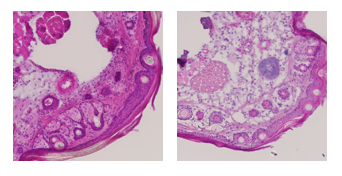

Pannexin1 deletion in lymphatic endothelium affects lymphatic function in a sex-dependent manner

The lymphatic network of capillaries and collecting vessels ensures tissue fluid homeostasis, absorption of dietary fats and trafficking of immune cells. Pannexin1 (Panx1) channels allow for the passage of ions and small metabolites between the cytosol and extracellular environment. Panx1 channels regulate the pathophysiological function of several tissues in a sex-dependent manner. Here, the authors led by GCIR Prof. Brenda Kwak, studied the role of Panx1 in lymphatic function, and potential sex-dependent differences therein, in Prox1-CreERT2Panx1fl/fl and Panx1fl/fl control mice. Panx1 expression was higher in lymphatic endothelial cells (LECs) of male mice. Lymphatic vessel morphology was not affected in Prox1-CreERT2Panx1fl/fl male and female mice. Lymphatic drainage was decreased by 25% in male Prox1-CreERT2Panx1fl/fl mice, but was similar in females of both genotypes. Accordingly, only male Prox1-CreERT2Panx1fl/fl mice exhibited tail swelling, pointing to interstitial fluid accumulation in males upon Panx1 deletion in LECs. Moreover, serum triglyceride and free fatty acid levels raised less in Prox1-CreERT2Panx1fl/fl mice of both sexes in an oral lipid tolerance test. Finally, the percentage of migratory dendritic cells arriving in draining lymph nodes was increased in Prox1-CreERT2Panx1fl/fl female mice, but was comparable between male mice of both genotypes. These results point to a LEC-specific role for Panx1 in the functions of the lymphatic system.